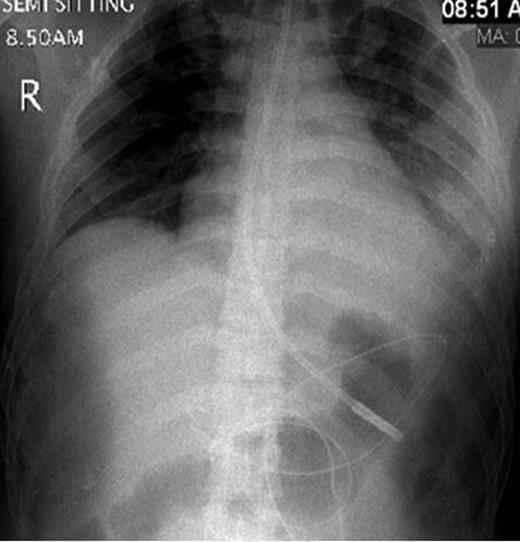

CT abdomen showing two hepatic lacerations in addition to minimal subhepatic and left subdiaphragmatic free fluid.